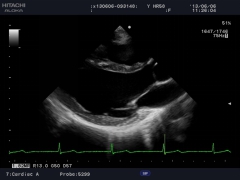

FAM全方位M型

對于許多非正常體位的病人,醫(yī)生很難得到滿意的標準圖象,這對一些必要的測量如心功能測量會帶來一定的影響,為此,阿洛卡開發(fā)出任意角度M型,并同時可以取三條取樣線,其中每一條取樣線都可以任意改變角度,3600旋轉(zhuǎn),不需要選擇旋轉(zhuǎn)點。取樣既可在實時條件下進行,也可在凍結(jié)后完成。為用戶提供了非常便捷的方法。